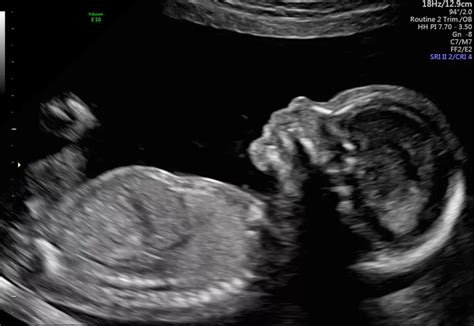

Alright guys, let’s get down to brass tacks. The 20-week scan, often called the anomaly scan or the mid-pregnancy ultrasound, is a crucial milestone during your pregnancy. Its primary purpose is to conduct a thorough anatomical survey of your developing baby. Think of it as a detailed check-up from head to toe, looking for any structural abnormalities or potential issues. This isn’t just about finding out the baby’s gender (though that’s a fun bonus for many!). The sonographer will meticulously examine everything: the baby’s brain, face (including lips and palate), spine, heart (checking the chambers and major vessels), kidneys, bladder, stomach, limbs (arms, legs, fingers, toes), and the umbilical cord. They’re also assessing the amount of amniotic fluid and checking the position and health of the placenta. In India, like in many other parts of the world, this scan is generally recommended between 18 and 22 weeks of gestation. It’s timed perfectly because by this point, the baby is well-developed enough for most major organs and structures to be visible and assessed. The accuracy of the scan depends on several factors, including the skill of the sonographer, the quality of the equipment, and how the baby is positioned. Sometimes, if the baby is in an awkward position or there’s a lot of maternal tissue, certain parts might be harder to see clearly, and a follow-up scan might be necessary. It’s important to go into this scan with realistic expectations. While it’s incredibly thorough, it’s not foolproof. Some very minor issues might not be detectable, and sometimes, subtle signs might lead to further investigations rather than an immediate diagnosis. The aim is to provide a comprehensive picture of your baby’s development and identify any concerns that might require further attention or management post-birth.